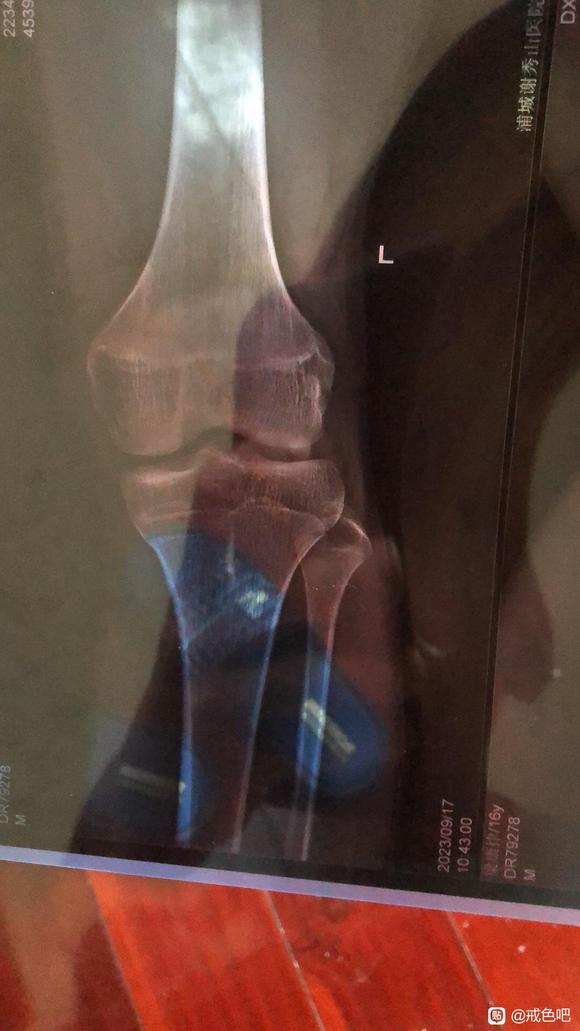

16.5周岁,遗传身高175,目前173戒了有机会到177吗,我身边跟我一个基因的同学都突破基因长到180了,拍了张腿骨骺线

现在有点接近闭合,长高趁这段时间,早睡早起,多运动多补钙,sy是会导致发育失常的,我就是发育期间sy,导致停留到173,你还有机会别走我的路了